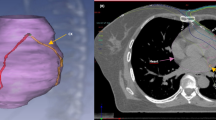

The esophageal cancer group consisted of 2 female and 14 male patients with a mean age of 67.6 years (range 48–85 years). Repeat MPI studies were performed after completion of RT at a mean interval of 7.0 months (median = 5.3 months) in this group of patients. The total radiation dose in 14/16 patients was 50.4 Gy, one patient received a total dose of 30.0 Gy and another patient received a total dose of 51.2 Gy. The mean heart radiation dose was 30.0 Gy (median = 30.0 Gy) and the mean heart volume irradiated was 734.7 cc (median = 685.8 cc). The mean V30 (mean heart volume receiving >30 Gy), V40 (mean heart volume receiving >40 Gy), and V50 (mean heart volume receiving >50 Gy) were 51, 31, and 16%; respectively. All patients in the esophageal cancer group received concurrent chemotherapy with RT. Five patients (31%) in the esophageal cancer group developed ischemia in the inferior segments which were in the RT field. Additionally, one patient developed anteroseptal ischemia after CRT which was not included in the RT field. The patients in the esophageal cancer group were followed for a mean interval of 14.6 months (median = 10.9 months, range = 2.8–34.8 months). During the follow-up interval seven patients (44%) developed cardiac complications (Table 2). One of these patients died (6%) of complete heart block and CHF at 12 months after CRT. This patient had no significant known cardiac disorders prior to CRT. Three of the patients who developed cardiac morbidities after CRT demonstrated ischemic changes on repeat MPI after CRT, and one of them was the patient who died of cardiac complications (Fig. 1). The remaining three patients who developed new MPI abnormalities after CRT did not suffer from cardiac morbidities. Thus, new MPI abnormalities after CRT were not predictive of future cardiac morbidities (P = 1.00). At the end of the follow-up period, 11/16 patients (69%) were deceased, 10 of whom died of noncardiac causes.

Short axis, vertical long axis and horizontal long axis slices of a stress MPI study before (a) and after CRT (b) demonstrating new ischemia (arrows) in a patient with esophageal cancer who died of complete heart block and worsening CHF 12.0 month after CRT. c Sagittal and coronal slices of the simulation CT with the RT plan demonstrating correlation of the irradiated part of the heart with the area of myocardial ischemia in (b)

Interestingly, this study has also confirmed our previously identified specific patterns of MPI abnormality of inferior wall ischemia noted in distal esophageal cancer patients [20] and anterior/septal ischemia pattern in centrally located lung cancer patients [21]. This inferior ischemia in esophageal cancer patients is usually due to the proximity of the more common distal esophageal tumors to the heart resulting in inclusion of the inferior wall of the left ventricle in the RT field. On the other hand central lung tumors are usually in close proximity to the anterior wall of the left ventricle when the tumor is on the left side and to the septum when it is on the right side resulting in inclusion of these walls in the RT field with consequent ischemic changes after CRT.